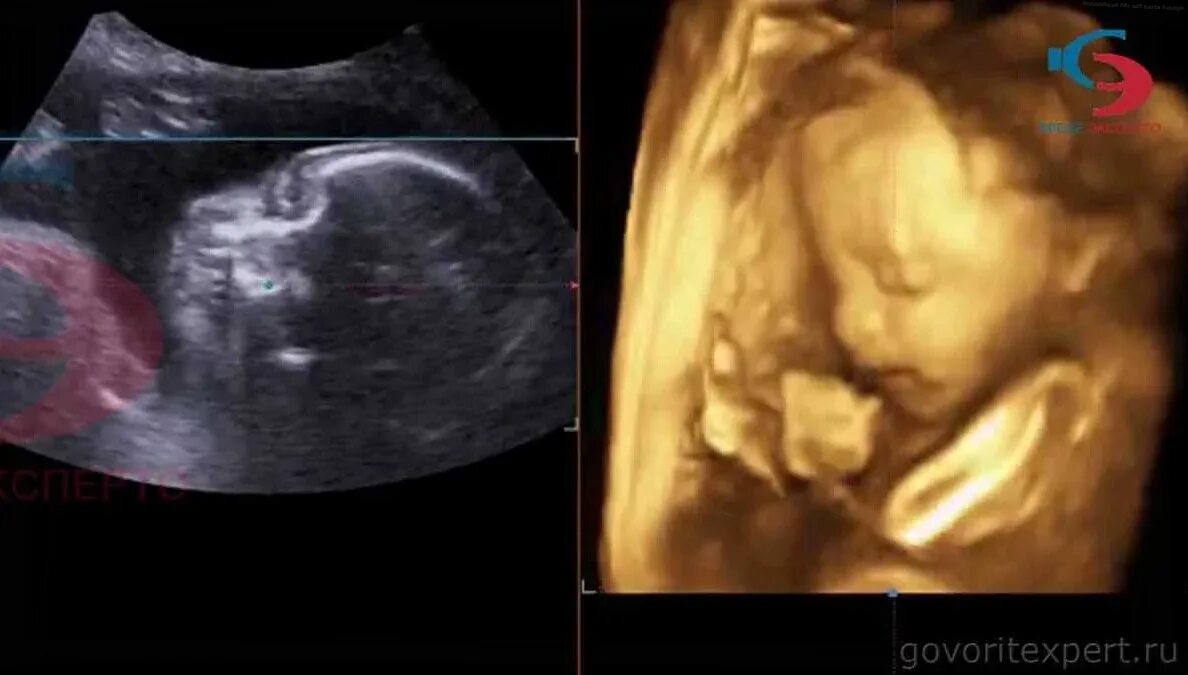

Второй скрининг 21 неделе